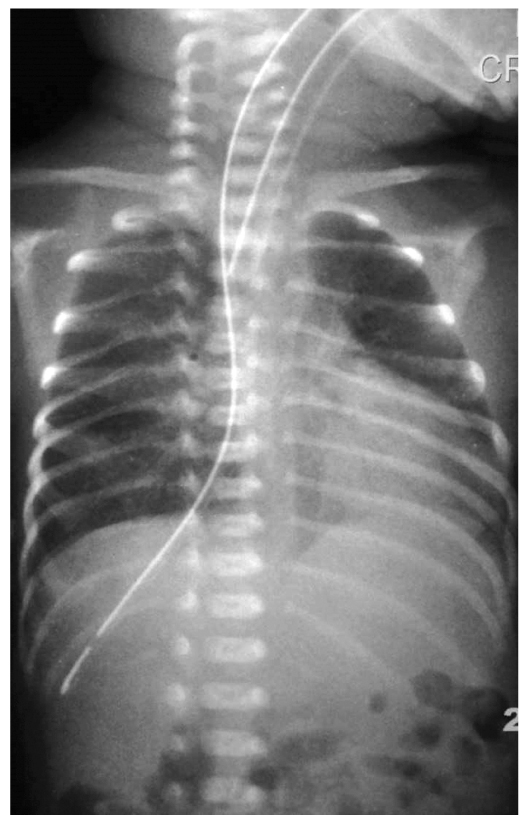

Перфорация пищевода в области глоточно-пищеводного перехода часто симулирует атрезию или врождённый стеноз пищевода. Травма происходит во время сложной интубации, когда производится несколько попыток введения интубационной трубки в дыхательные пути ребёнка. В этот момент интубационная трубка расслаивает стенку глотки и пищевода, создавая своеобразный тоннель или карман в тканях средостения. При последующем (после интубации) введении желудочного зонда в пищевод возникает ощущение препятствия на расстоянии, типичном для детей с атрезией пищевода, и провести зонд глубже не удаётся, а если зонд все-таки продвинулся вниз, то конец его будет визуализироваться вне тени пищевода и желудка. В клинической картине преобладают дисфагия, слюнотечение, выделение крови из ротовой полости и носа, нарастание респираторного дистресса. Все эти симптомы, кроме кровоточивости из полости рта и носа, характерны и для атрезии или врождённого стеноза пищевода, которые чаще всего и начинают подозревать у ребёнка. Результат рентгенографии только усиливает подозрение на порок пищевода (рис. 5).

Рис. 5. Контрастная рентгенография органов грудной и брюшной полости: имитация стеноза пищевода

Fig. 5. Thoracic and abdominal contrast stud: mimicing a picture of esophageal stricture

Однако следует обратить внимание на нечёткие фестончатые края скопления контраста в «верхнем сегменте» пищевода (на самом деле в кармане средостения, созданного интубационной трубкой) и на небольшое количество контраста, спустившегося по пищеводу или средостению вниз к желудку. Для исключения атрезии пищевода мы дополнительно выполняли фарингоэзофагоскопию ультратонким аппаратом.